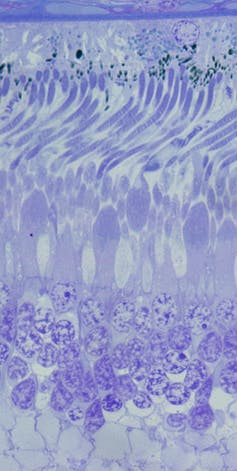

Retina de mono.

Retina de mono.Author provided

Esa reposición no la hacen directamente ellos, sino las células del epitelio pigmentario, que también se encargan de mediar entre los capilares sanguíneos y los fotorreceptores, pasándoles a estos los nutrientes y vertiendo sus desechos de vuelta a la sangre.

Las células del epitelio pigmentario son unas auténticas heroínas, que cumplen con su misión con una gran destreza y de forma continuada todos los días de nuestra vida. No hay que olvidar que estas células son las mismas desde que nacemos hasta que dejamos este mundo.

Para hacernos una idea de la ingente cantidad de trabajo diario que realizan a lo largo de los años, hay que tener en cuenta que en nuestros ojos tenemos aproximadamente 130 millones de bastones y unos 7 millones de conos. Y que en la zona de máxima densidad de fotorreceptores de nuestra retina nos encontramos con unos 28 fotorreceptores por célula de epitelio pigmentario. Por tanto, el epitelio pigmentario tiene un trabajo extenuante.

Tan cansado y demandante que un fallo en el engranaje de esta maquinaria en la que la ejecución de varias tareas de forma eficiente durante muchos años es crucial, puede conllevar enfermedades graves de retina e incluso a cegueras irreversibles.